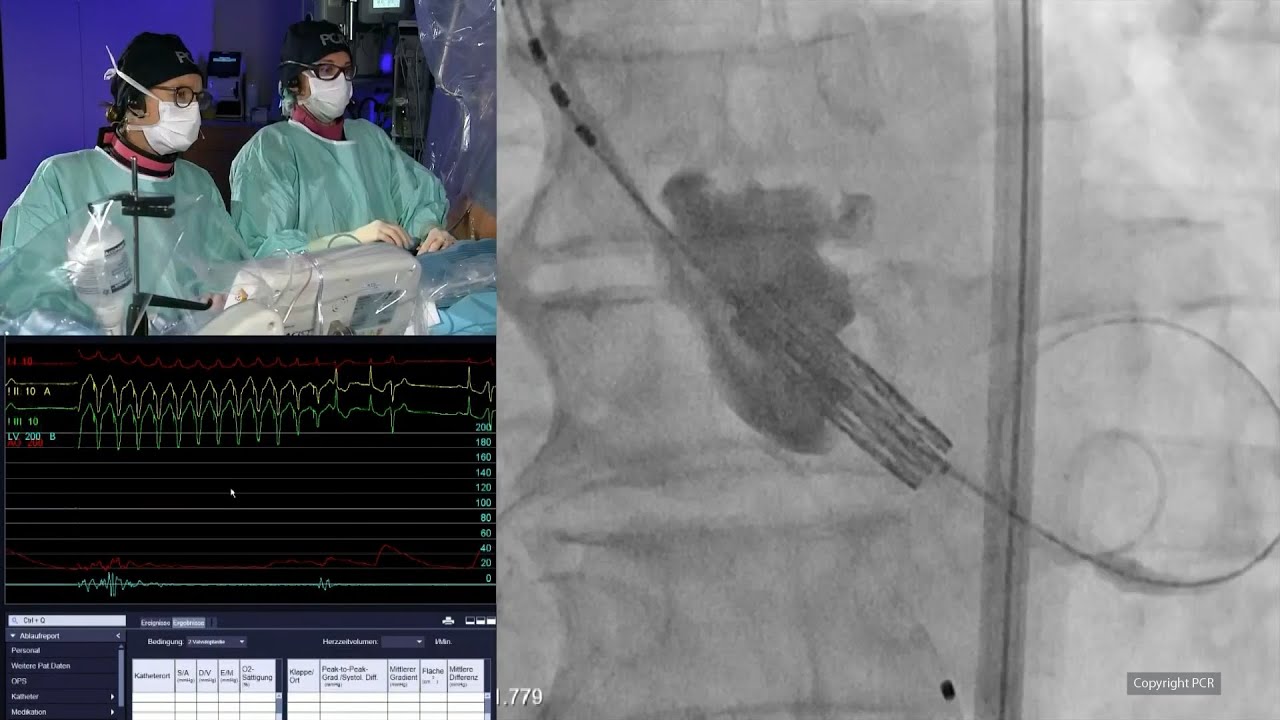

Transcatheter tricuspid valve repair: LIVE Educational Case from University Medical Center - Mainz, Germany